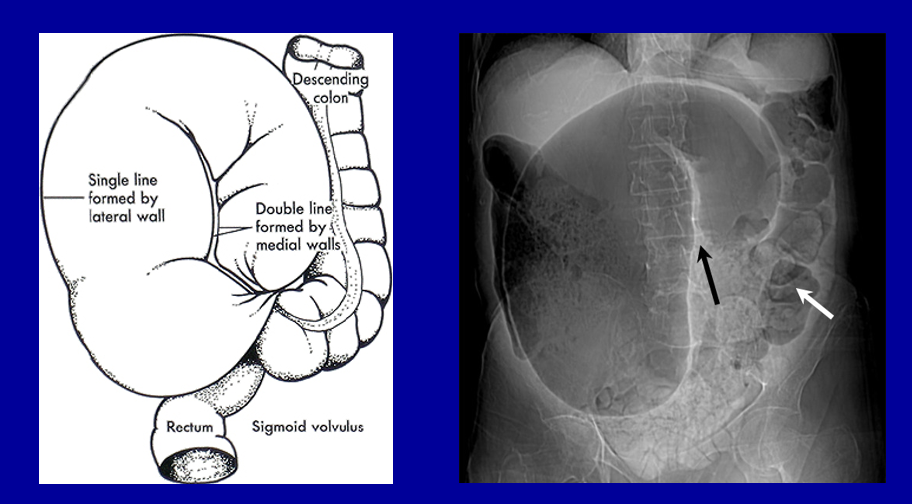

What is shown in the AXR?

Sigmoid volvulus

Just to look at and differentiate from a sigmoid volvulus